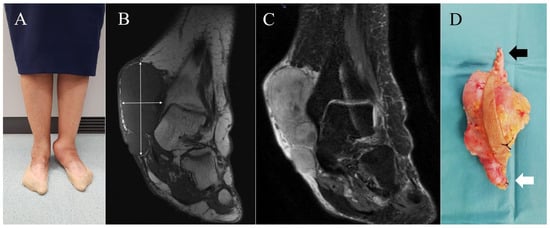

Malignant Tumours Presenting as Chronic Leg or Foot Ulcers

22 May 2021

Our purpose was to collect data on the incidence of malignant skin tumours presenting as chronic leg or foot ulcers in a tertiary centre, and to analyse the frequency and type of initial clinical misdiagnoses in these cases. A retrospective chart rev...